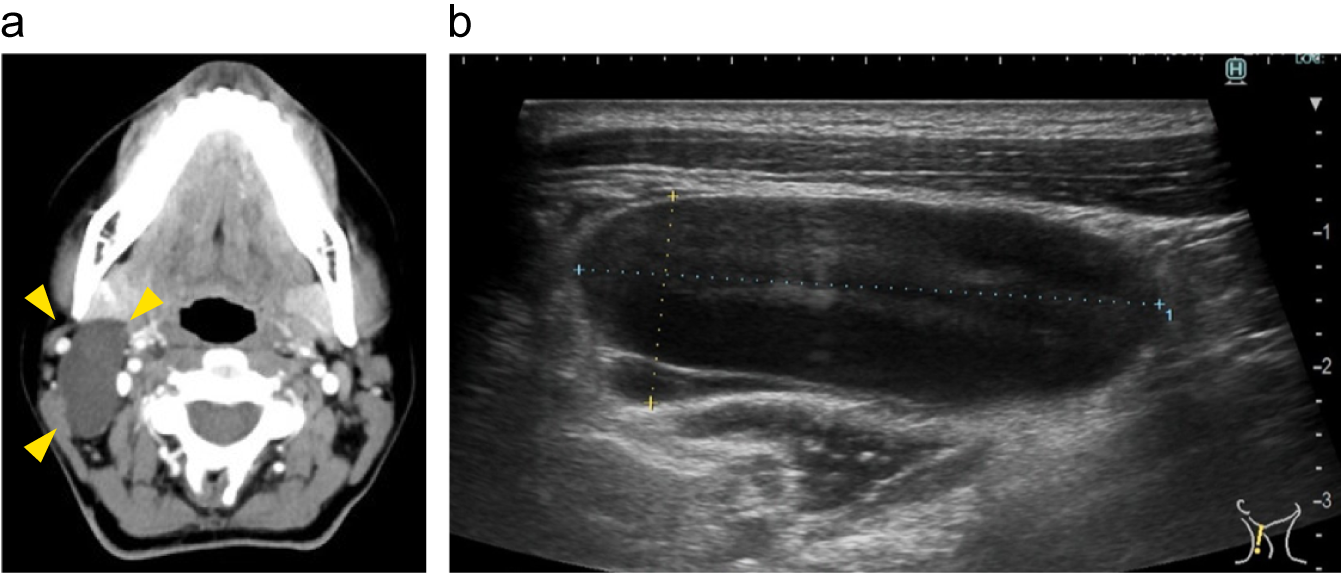

症例2:側頸嚢胞

a:術前造影CT画像軸位断、b:術前US画像 境界明瞭な単房性嚢胞を認める。

出典

img

1: 著者提供